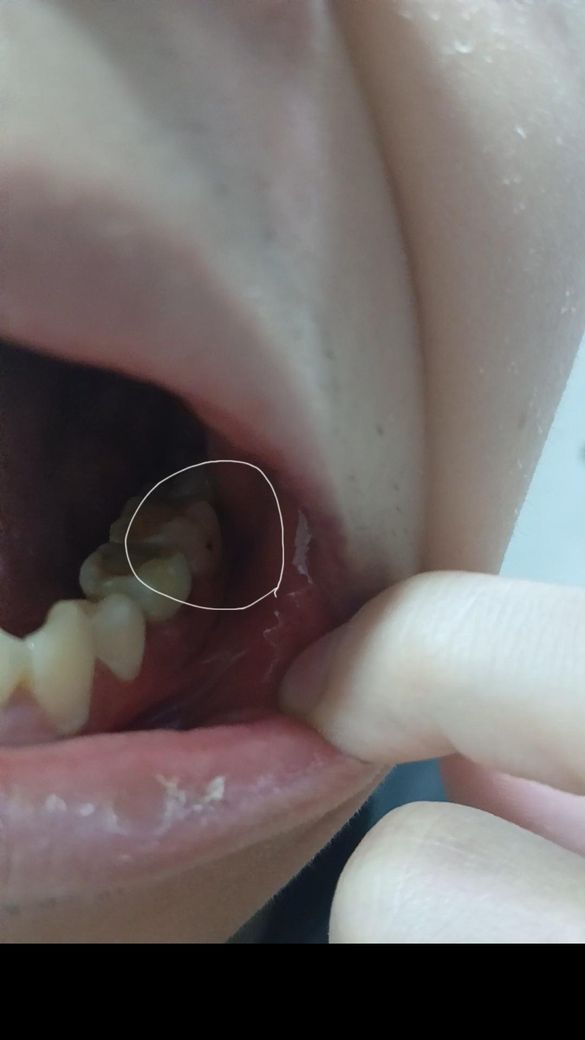

이거충치인가요? 착색인가요? 알고싶습니다.

자세히보니 레진한이에 옆면에 검은점이 있더라고요

레진치료밭은 이옆면에 검은점이 있는데 착색일까요? 아니면 충치일까요?

표면매끄럽고 아프지않습니다. 착색이 검정색일수있나요? 시간지나면서 원래충치가 보일수있는건가요?

해당 부위는 첫번째 큰어금니의 볼쪽 구덩이(협측소와, buccal pit)라 불리는 곳으로 안으로 움푹 들어가있어 위생 관리가 어려워 충치가 잘 생기는 곳이기도 합니다.